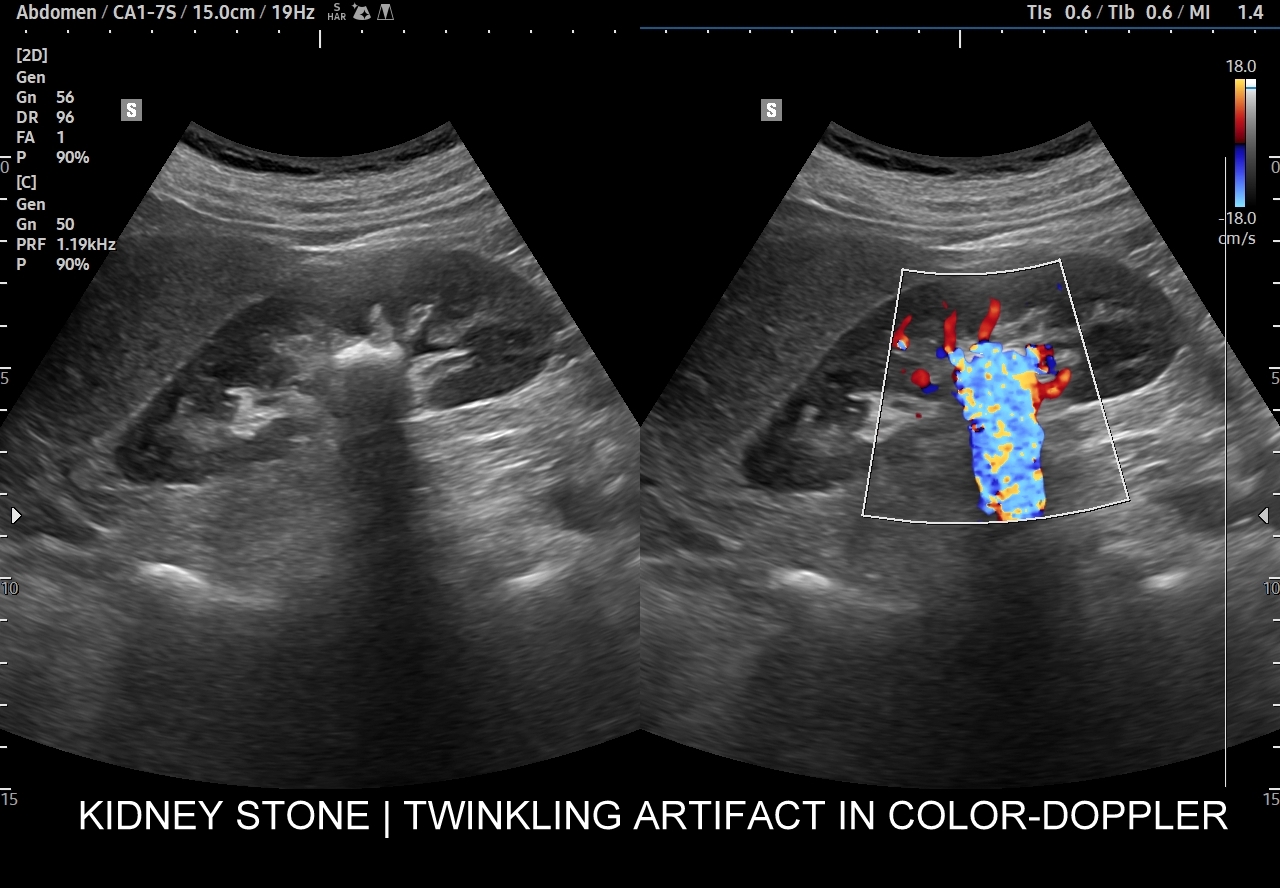

Badania obrazowe służące wykrywaniu kamicy moczowej to badanie RTG, CT, lecz przede wszystkim badanie USG. W badaniu USG nerek w prezentacji B kamica nerkowa widoczna jest w sytuacji, gdy złogi są odpowiednio uwapnione, odpowiednio duże oraz nie zlewają się z zatoką tłuszczową miedniczki nerki. Zasadniczo złogi w trybie B będą widoczne wyraźniej, gdy położone są w miąższu nerki; z kolei w miedniczce nerkowej, gdy są na tyle duże, że dają artefakt cienia. Czasem w celu uwidocznienia złogu przydatne jest wyłączenie wspomagania typu x-beam.

Ważnym trybem pomocniczym jest color-Doppler, w którym to trybie uzyskuje się tzw. artefakt migotania, często nawet na bardzo drobnych złogach niewidocznych w trybie B. Uzyskanie efektu migotania jest niestety zależne o jakości aparatury USG, a także od ustawień Dopplera i software’u.

W modalnościach dopplerowskich oprócz prezentacji color-Doppler artefakt migotania pojawia się także w trybie Dopplera spektralnego. Otóż po umieszczeniu bramki dopplerowskiej na złogu uzyskuje się charakterystyczny, dźwiękowy objaw trzeszczenia, a na obrazie wykresu wypełnienie sygnałem całego spektrum częstotliwości.